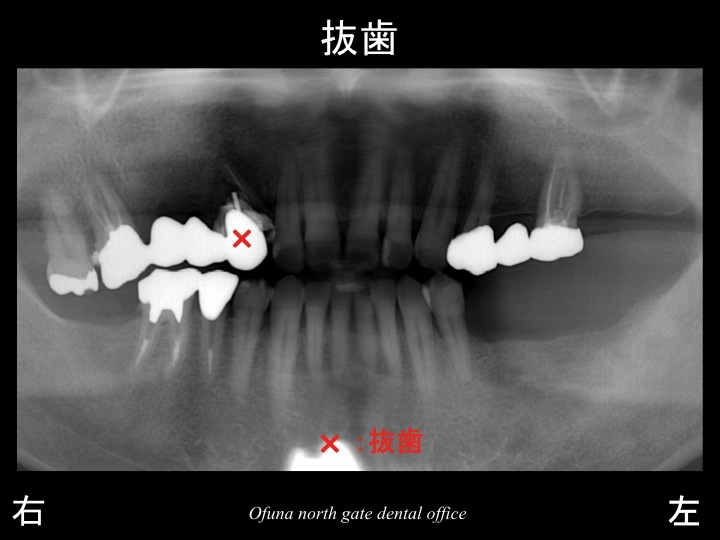

初診時は、以下のような状態で来院されました。

下顎の左側の奥歯がかなり以前から欠損していました。

そのため、食事のほとんどを右側で食べることになっていました。

ところが、少し前から上顎の左側の奥歯で噛むことができなくなってきました。

上顎左側が歯根破折 していたのです。

歯根破折 についてはこのブログでも良く紹介する内容です。

歯根破折 している場合、抜歯となることがほとんどです。

この歯を抜歯すると奥歯では噛めなくなるとの思いから

当医院を受診された患者様です。